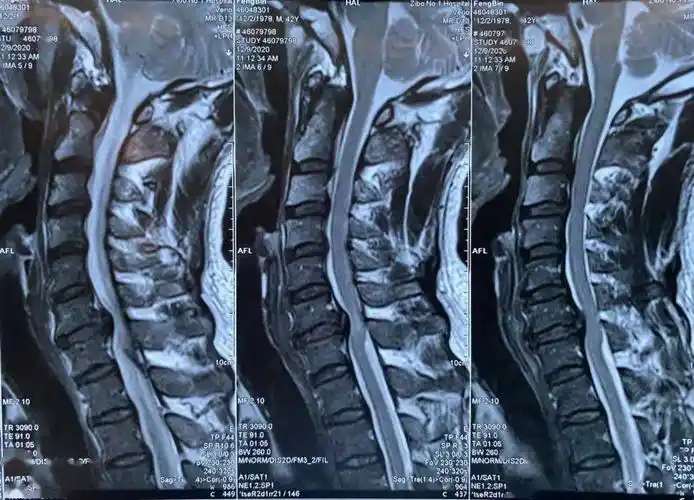

颈椎ct:后纵韧带钙化.该患者同样有手术指征.

脊髓型颈椎病术前ct片脊髓型颈椎病术前x线正,侧位片患者为42岁男性